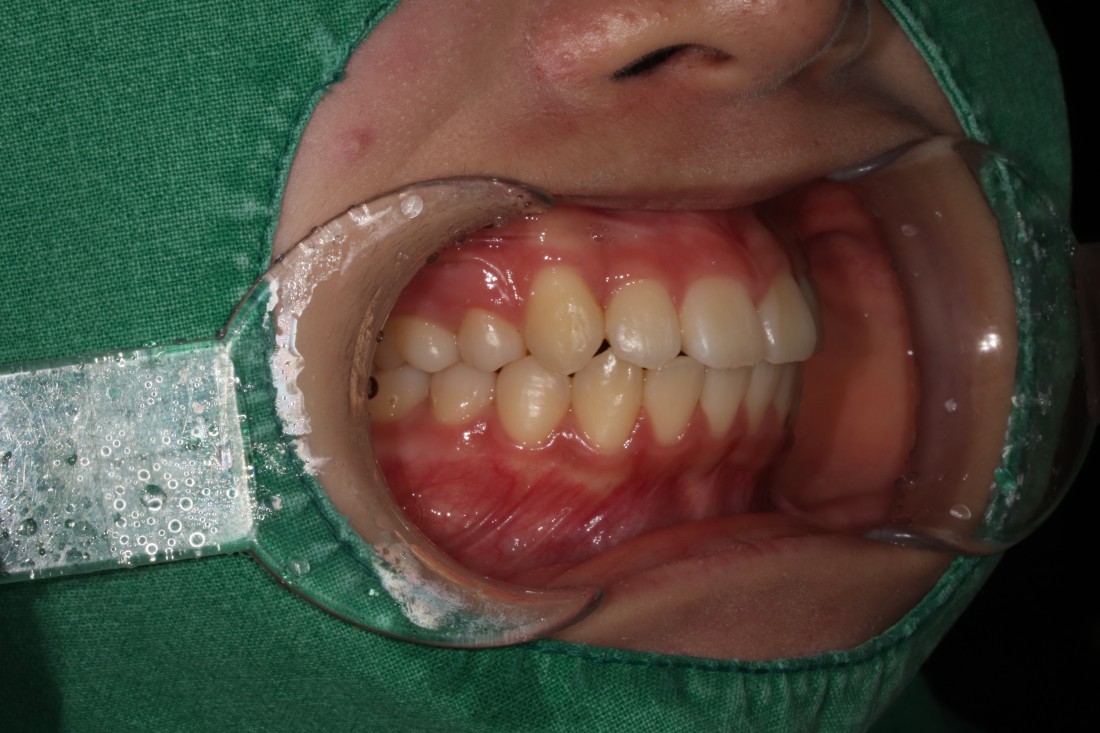

광주 발치교정이 필요한 대표적인 케이스는

돌출입의 경우인데요.

위, 아래 입술이 튀어나와 있거나

웃을 때 잇몸이 많이 보이는 경우,

혹은 입을 다물었을 때

턱에 힘이 많이 들어간다면

돌출입을 의심해볼 수 있습니다.

이런 경우에도 치아가 전체적으로

앞쪽으로 위치해서 입술을 밀어내고 있기 때문에

공간을 확보하기 위하여

광주 발치교정을 진행하는 케이스입니다.